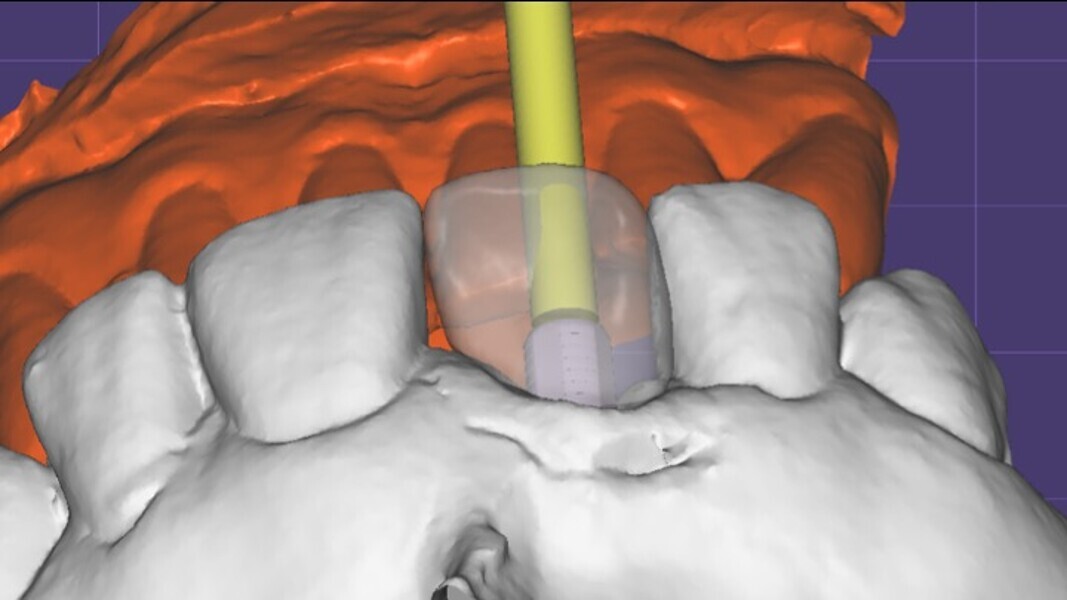

Figura 6. A pesar del defecto óseo, siempre buscamos la posibilidad de crear un nuevo alveolo quirúrgico que emerja por la zona del cíngulo de los dientes adyacentes, es decir, el margen de emergencia adecuado. En estos defectos, intentamos siempre el anclaje en profundidad con implantes largos de unos 16 mm debido al gran defecto existente. Es la única forma de que la estabilidad primaria del implante permita realizar una Prótesis Inmediata.